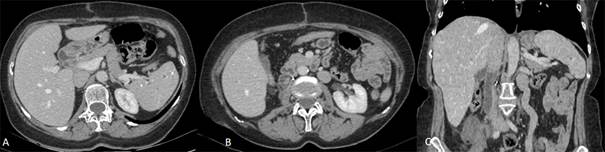

Presenta buena evolución en el posoperatorio, iniciándose anticoagulación a las 12 hs del postoperatorio, inicialmente con heparina de bajo peso molecular, y luego con anticoagulantes orales, la cual se mantiene durante el primer año debido a que presenta área de trombosis con flujo conservado en la prótesis (figura 3).

Figura 3: TC de abdomen en fase portal, post operatorio. A) Imagen axial donde se observa remanente de VCI permeable de calibre conservado B) y C) reconstrucciones axiales y coronales que muestran prótesis interpuesta de VCI parcialmente trombosada con canal de flujo permeable.